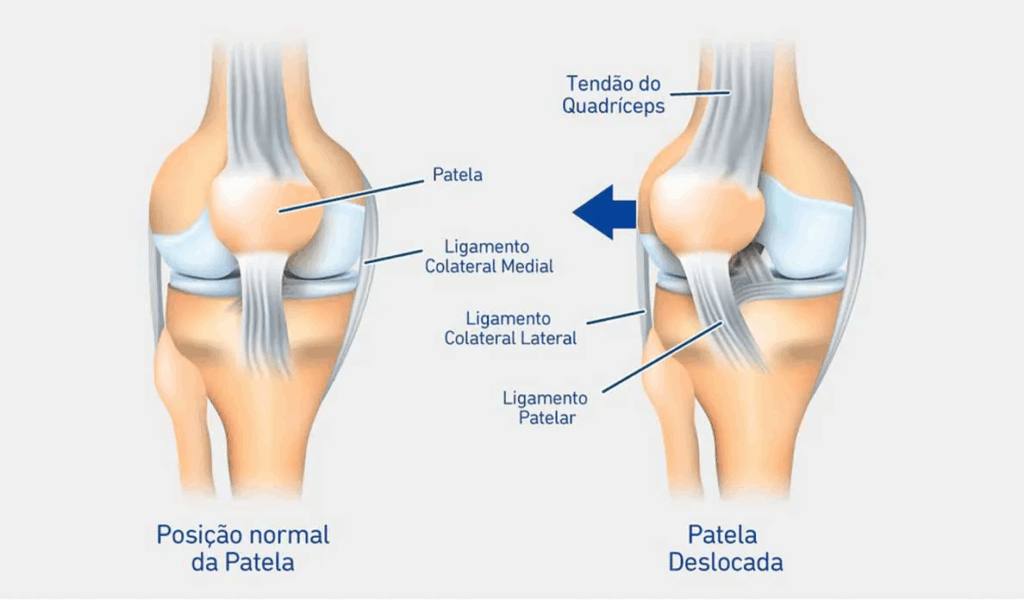

4. Condromalácia avançada com desalinhamento da patela

Quando a patela está “fora do trilho”, o tratamento costuma ser cirúrgico.